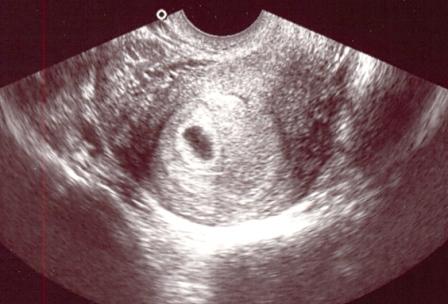

Merthogy ma délben voltam dokinál és 5,5 hetes vagyok!!!! :D :D :D :D :D

Csináltak ultrahangot, van rajta petezsák, szívhang még nincsen, de korai is lenne. 2 hét múlva újra nézzük. Itt a képecske:

Kép